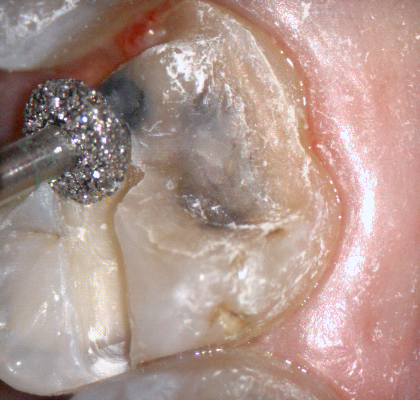

The following pictures depict the sequence of burs we recommend that you use to finish a preparation quickly. While patient is getting numb, take a quick look at the clearance you will need to reach proper material thickness. Once the quadrant is isolated with isolite and optragate, take an occlusal router bur and create a trough to gain the proper depth. Follow that with a flat disk, and you can quickly reduce the occlusal height.

A shoulder bur of .8 mm thickness can help you reduce the interproximal areas as well as the buccal and lingual margin lines. Before finishing the prep, place hemostatic agent like expasyl in the sulcus and place retraction cord. while it is setting, check your reduction. If you need more space, now is the time to reduce some more.